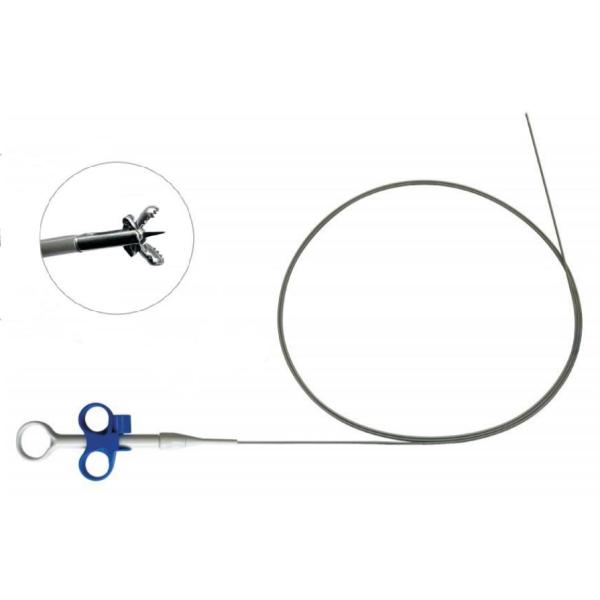

| Disposable Snare Foreign Body Forceps: The disposable snare foreign body forceps are designed for the removal of foreign bodies from the body's internal cavities or lumens. It is equipped with a snare-like mechanism that can be opened and closed to capture and retrieve foreign objects. The forceps are disposable, ensuring a hygienic and safe approach to foreign body removal. Plasma system technology can be integrated with the forceps to provide additional benefits such as cauterization or hemostasis during the removal procedure. |